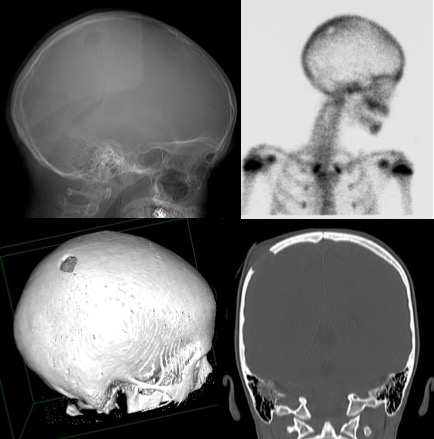

4 L’histiocytose de la voûte crânienne est la plus fréquentes des tumeurs osseuses, et elle peut se rencontrer dans des contextes divers : au décours d’une virose ou d’un vaccin (4a), après un traumatisme (4c) ou de façon isolée (4b), ou encore dans le cadre d’une maladie systémique. Son évolution naturelle typique est cyclique avec un début rapidement progressif, voire même aigu, des douleurs, puis une stabilisation suivie d’une régression spontanée avec réossification (4d). Étant donné le diagnostic différentiel avec des tumeurs beaucoup plus agressives, une intervention à visée de diagnostic histopathologique (curetage biopsique simple) est souvent indiquée.

5 le progonome mélanotique, reclassé avec les tumeurs embryonnaires de type PNET est une tumeur rare du jeune nourrisson, souvent à la peau foncée, et se développe typiquement à partir d’une fontanelle, de manière rapide voire explosive.

6-8 Parmi les tumeurs agressives localisées à la voûte crânienne, on retrouve les sarcomes (6), Ewing et autres ; les métastases (7), en particulier d’un neuroblastome (qui peut être diagnostiqué sur le dosage des catécholamines urinaires) ; et les kystes anévrysmaux (8)